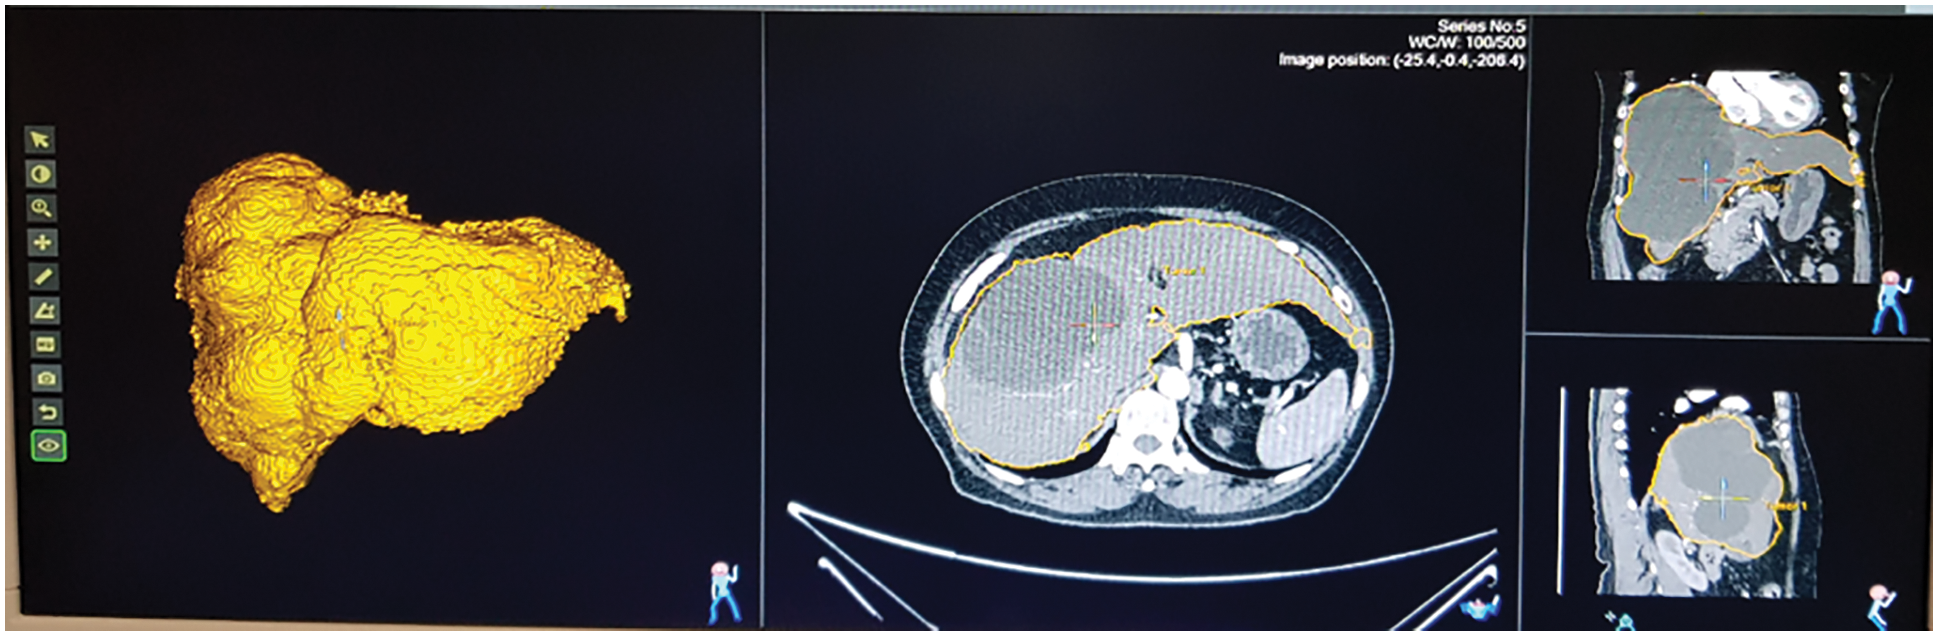

The fatty liver performance is analyzed through ultrasound image and Q values from fatty liver sensor. The tunable Q wavelet transform signal parameters is correlated with ultrasound values. Fig. 12 shows the ultrasound value of severe fatty liver patient. The total liver volume is 2442.13 cc, right liver volume is 554 cc and left liver volume is 1888 cc. The severe fatty liver signal obtained from female patient at the age 61.

Figure 12: Ultrasound of severe fatty liver patient